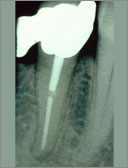

Röntgenbild unmittelbar vor Extraktion

Nur der bukkale Wurzelkanal ist gefüllt.

In seinem lingualen Anteil sind Undichtigkeiten auszumachen.

Der linguale Wurzelkanal zweigt rechtwinklig vom gemeinsamen koronalen Wurzelkanalverlauf ab.

Im koronalen Wurzeldrittel sind bukkal und lingual des Stiftaufbaus

unbearbeitete finartige Ausläufer der Pulpahohlräume zu erkennen.

Vom lingualen Ausläufer sind Pigmente bis tief in das Dentin diffundiert.

Zwischen Wurzelstift und Guttaperchafüllung befindet sich eine

Ansammlung von röntgenkontrastarmem Kompositkleber (Panavia).